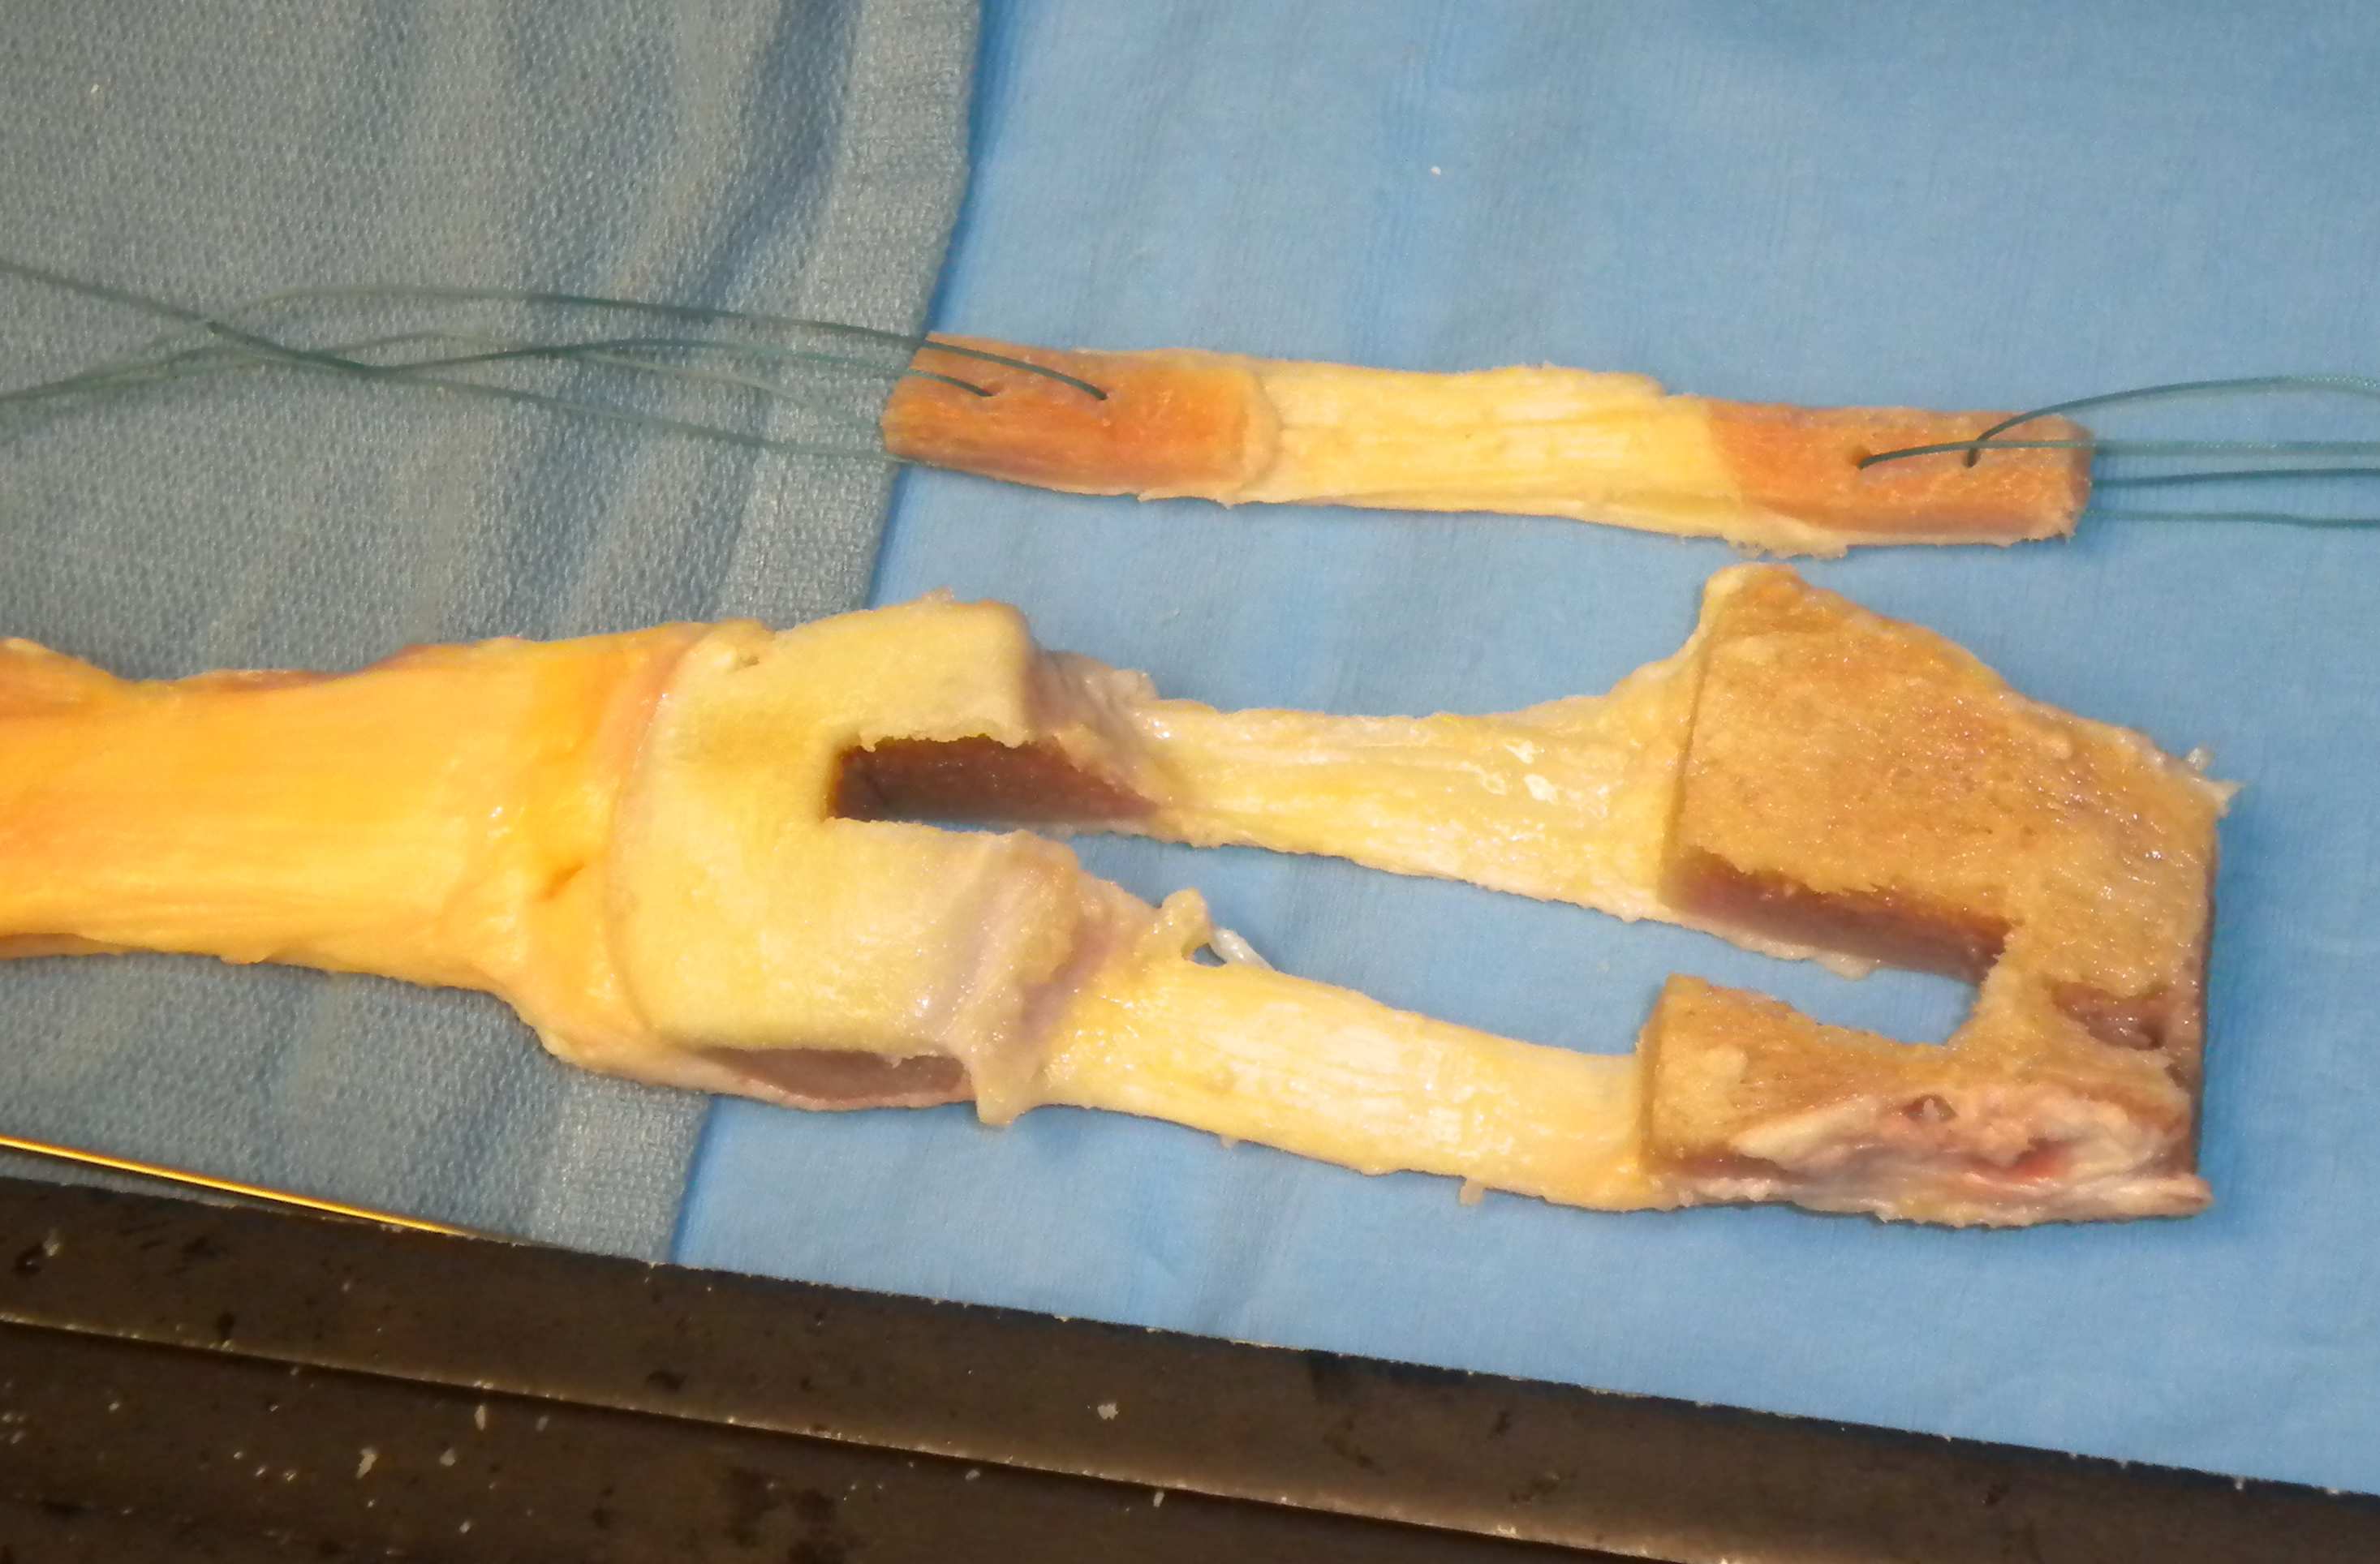

Drill holes x 2 in each bony block

- pass 1 ethibonds x 2 with suture passer

- tension

Length of bone femoral side

- usually 20 mm on femoral side

Length of bone on tibial side

- best to keep this side long / take from tibial end of graft

- so keep bone graft long

- at least 30 mm